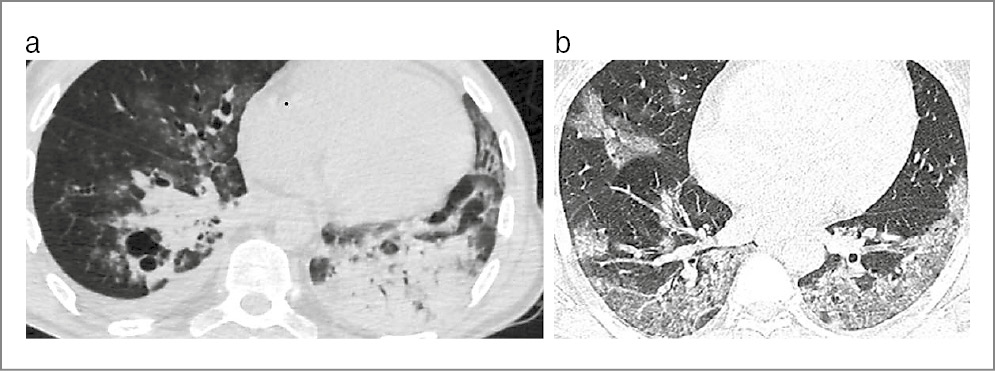

На КТ ОГК визуализировался комплекс одновременного сочетания 4 патологических синдромов: диссеминации, патологии плевры, усиления легочного рисунка и аденопатии. Синдром диссеминации представлен очагами разных размеров (от мелких до крупных) и интенсивности (от низкой до высокой), с тенденцией к слиянию и образованию инфильтратов негомогенного характера, с деструкцией легочной ткани и бронхогенным обсеменением. Синдром поражения плевры проявлялся уплотнением междолевой и париетальной плевры, а более чем у 1/2 пациентов – с развитием экссудативного плеврита или эмпиемы плевры. Синдром усиления и деформации легочного рисунка имел «сетчатый» характер вследствие развития интерстициальной пневмонии при лимфогематогенной диссеминации, с диффузным понижением прозрачности легочной ткани, развитием кистозно-дистрофических изменений и участками консолидации по типу «матового стекла». Синдром аденопатии представлен двусторонним увеличением внутригрудных лимфатических узлов с инфильтративными изменениями по периферии.

Таким образом, у больных группы 1А с коморбидностью ДТЛ, КВП и ПЦП, 1Б с коморбидностью ДТЛ и ПЦП и без КВП, 2А с коморбидностью ДТЛ, КВП и ПЦП и 2Б с коморбидностью ДТЛ и ПКП и без КВП, с IVВ-стадией ВИЧ-инфекции, выраженным ИД, в фазе прогрессирования и в отсутствие АРВТ клиническая картина характеризуется синдромом интоксикации, общими воспалительными и респираторными проявлениями, практически одинакова и неспецифична, а особенности клинического течения коморбидного заболевания возможно определить только при выявлении конкретного возбудителя. В качестве примеров приведены КТ ОГК больных IVВ-стадией ВИЧ-инфекции с ИД, в фазе прогрессирования и в отсутствие АРВТ, иллюстрирующие сходство визуализации патологических изменений во всех группах (рис. 1, 2).

Рис. 1. КТ ОГК. Аксиальная проекция, режим легочного окна: a – пациент 42 лет с IVВ-стадией ВИЧ-инфекции с ИД, в фазе прогрессирования, без АРВТ и с верифицированной коморбидностью ДТЛ, КВП и ПЦП; b – пациент 39 лет с IVВ-стадией ВИЧ-инфекции с ИД, в фазе прогрессирования, без АРВТ и с верифицированной коморбидностью ДТЛ и ПЦП.

Как видно на рис. 1 и 2, на КТ ОГК визуализируются однотипные четыре синдрома: диссеминации, патологии плевры, усиления и деформации легочного рисунка с участками «матового стекла» и аденопатии.

Таким образом, на КТ ОГК у больных с коморбидностью туберкулеза органов дыхания (ТОД), КВП и ПЦП или ТОД и ПЦП и без КВП, IVВ-стадией ВИЧ-инфекции, в фазе прогрессирования и в отсутствие АРВТ с ИД визуализируются однотипные синдромы наслоения нескольких патологий, дифференцировать которые не представляется возможным, что требует своевременной диагностики с использованием микробиологических, молекулярно-генетических и иммунологических исследований для выявления M. tuberculosis, SARS-CoV-2, P. jiroveci, S. pneumoniae для адекватного своевременного этиологического лечения.